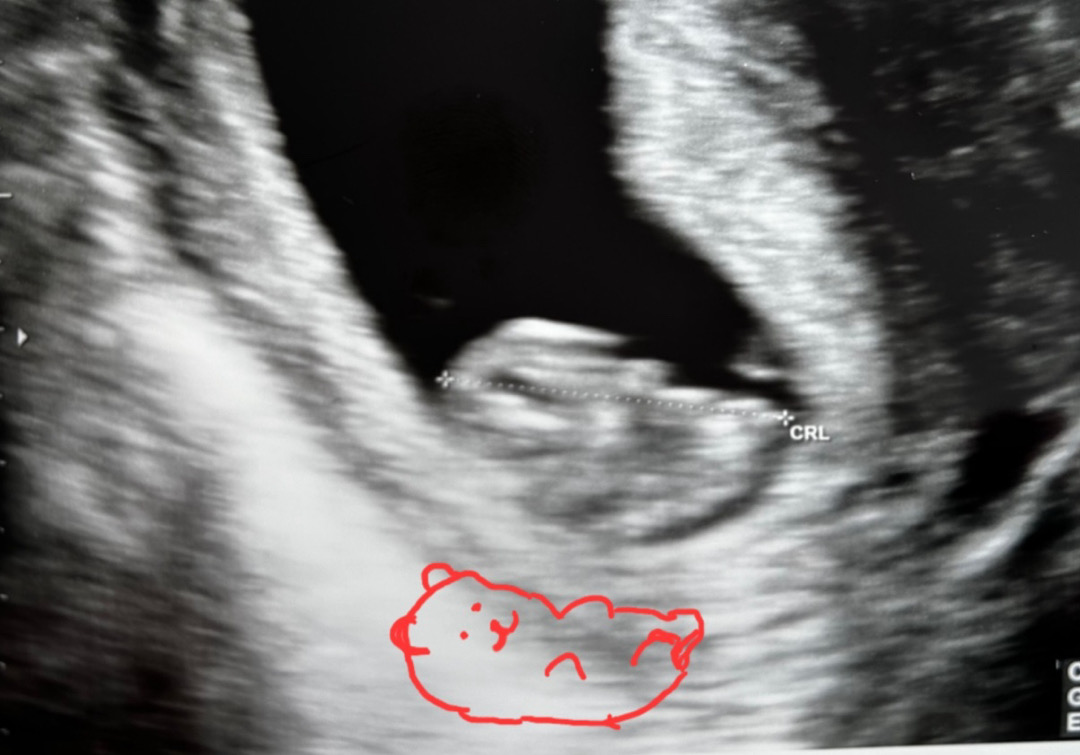

9주 젤리곰?? 보고 왔어요~

안녕하세요~ 늘 눈팅하다가 처음 글 올려봐요^^ 9주 되서 배초음파로 아가보고 왔는데 질초음파보다는 선명하지 않게 나온것 같아서 쬐끔 아쉬웠어요 ㅜㅜㅜㅜ 다들 젤리곰 볼 수 있다고 해서 기대하고 초코우유도 먹고 갔는데 ㅋㅋㅋㅋㅋㅋ 팔로 보이는게 살짝 움직이는 거 봤네요^^;; 신랑이 같이갔는데 아쉬워하는 저를 위해 나름 젤리곰을 열심히 그려줬어요 ㅋㅋㅋㅋㅋ 근데 머리 옆에 토끼귀같이 생긴 길쭉한 거는 뭘까요?? ㅋㅋㅋㅋㅋ